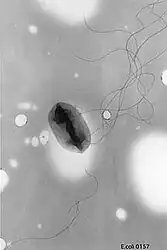

![]() Escherichia coli O157:H7 w transmisyjnym mikroskopie elektronowym | |

Escherichia coli O157:H7

Escherichia coli O157:H7 jest najczęstszym w Stanach Zjednoczonych i Kanadzie serotypem EHEC[2][3]. Wywołuje choroby układu pokarmowego i moczowego. Powoduje ona biegunkę, powikłania schorzeń nadnercza oraz groźny zespół hemolityczno-mocznicowy. Główną przyczyną infekcji bakterią jest spożycie wołowiny niepoddanej obróbce termicznej. Śmiertelność zakażeń tym serotypem wśród dzieci wynosi 5%.